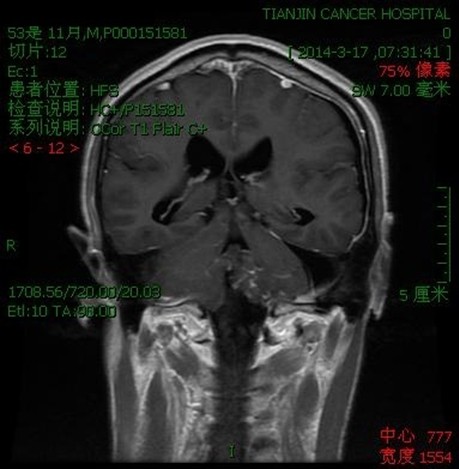

病例一:张**。女性,52岁。查体发现枕骨大孔区占位入院。临床诊断:枕骨大孔区腹侧脑膜瘤。术式:远外侧入路。术后病理脑膜瘤。

术后